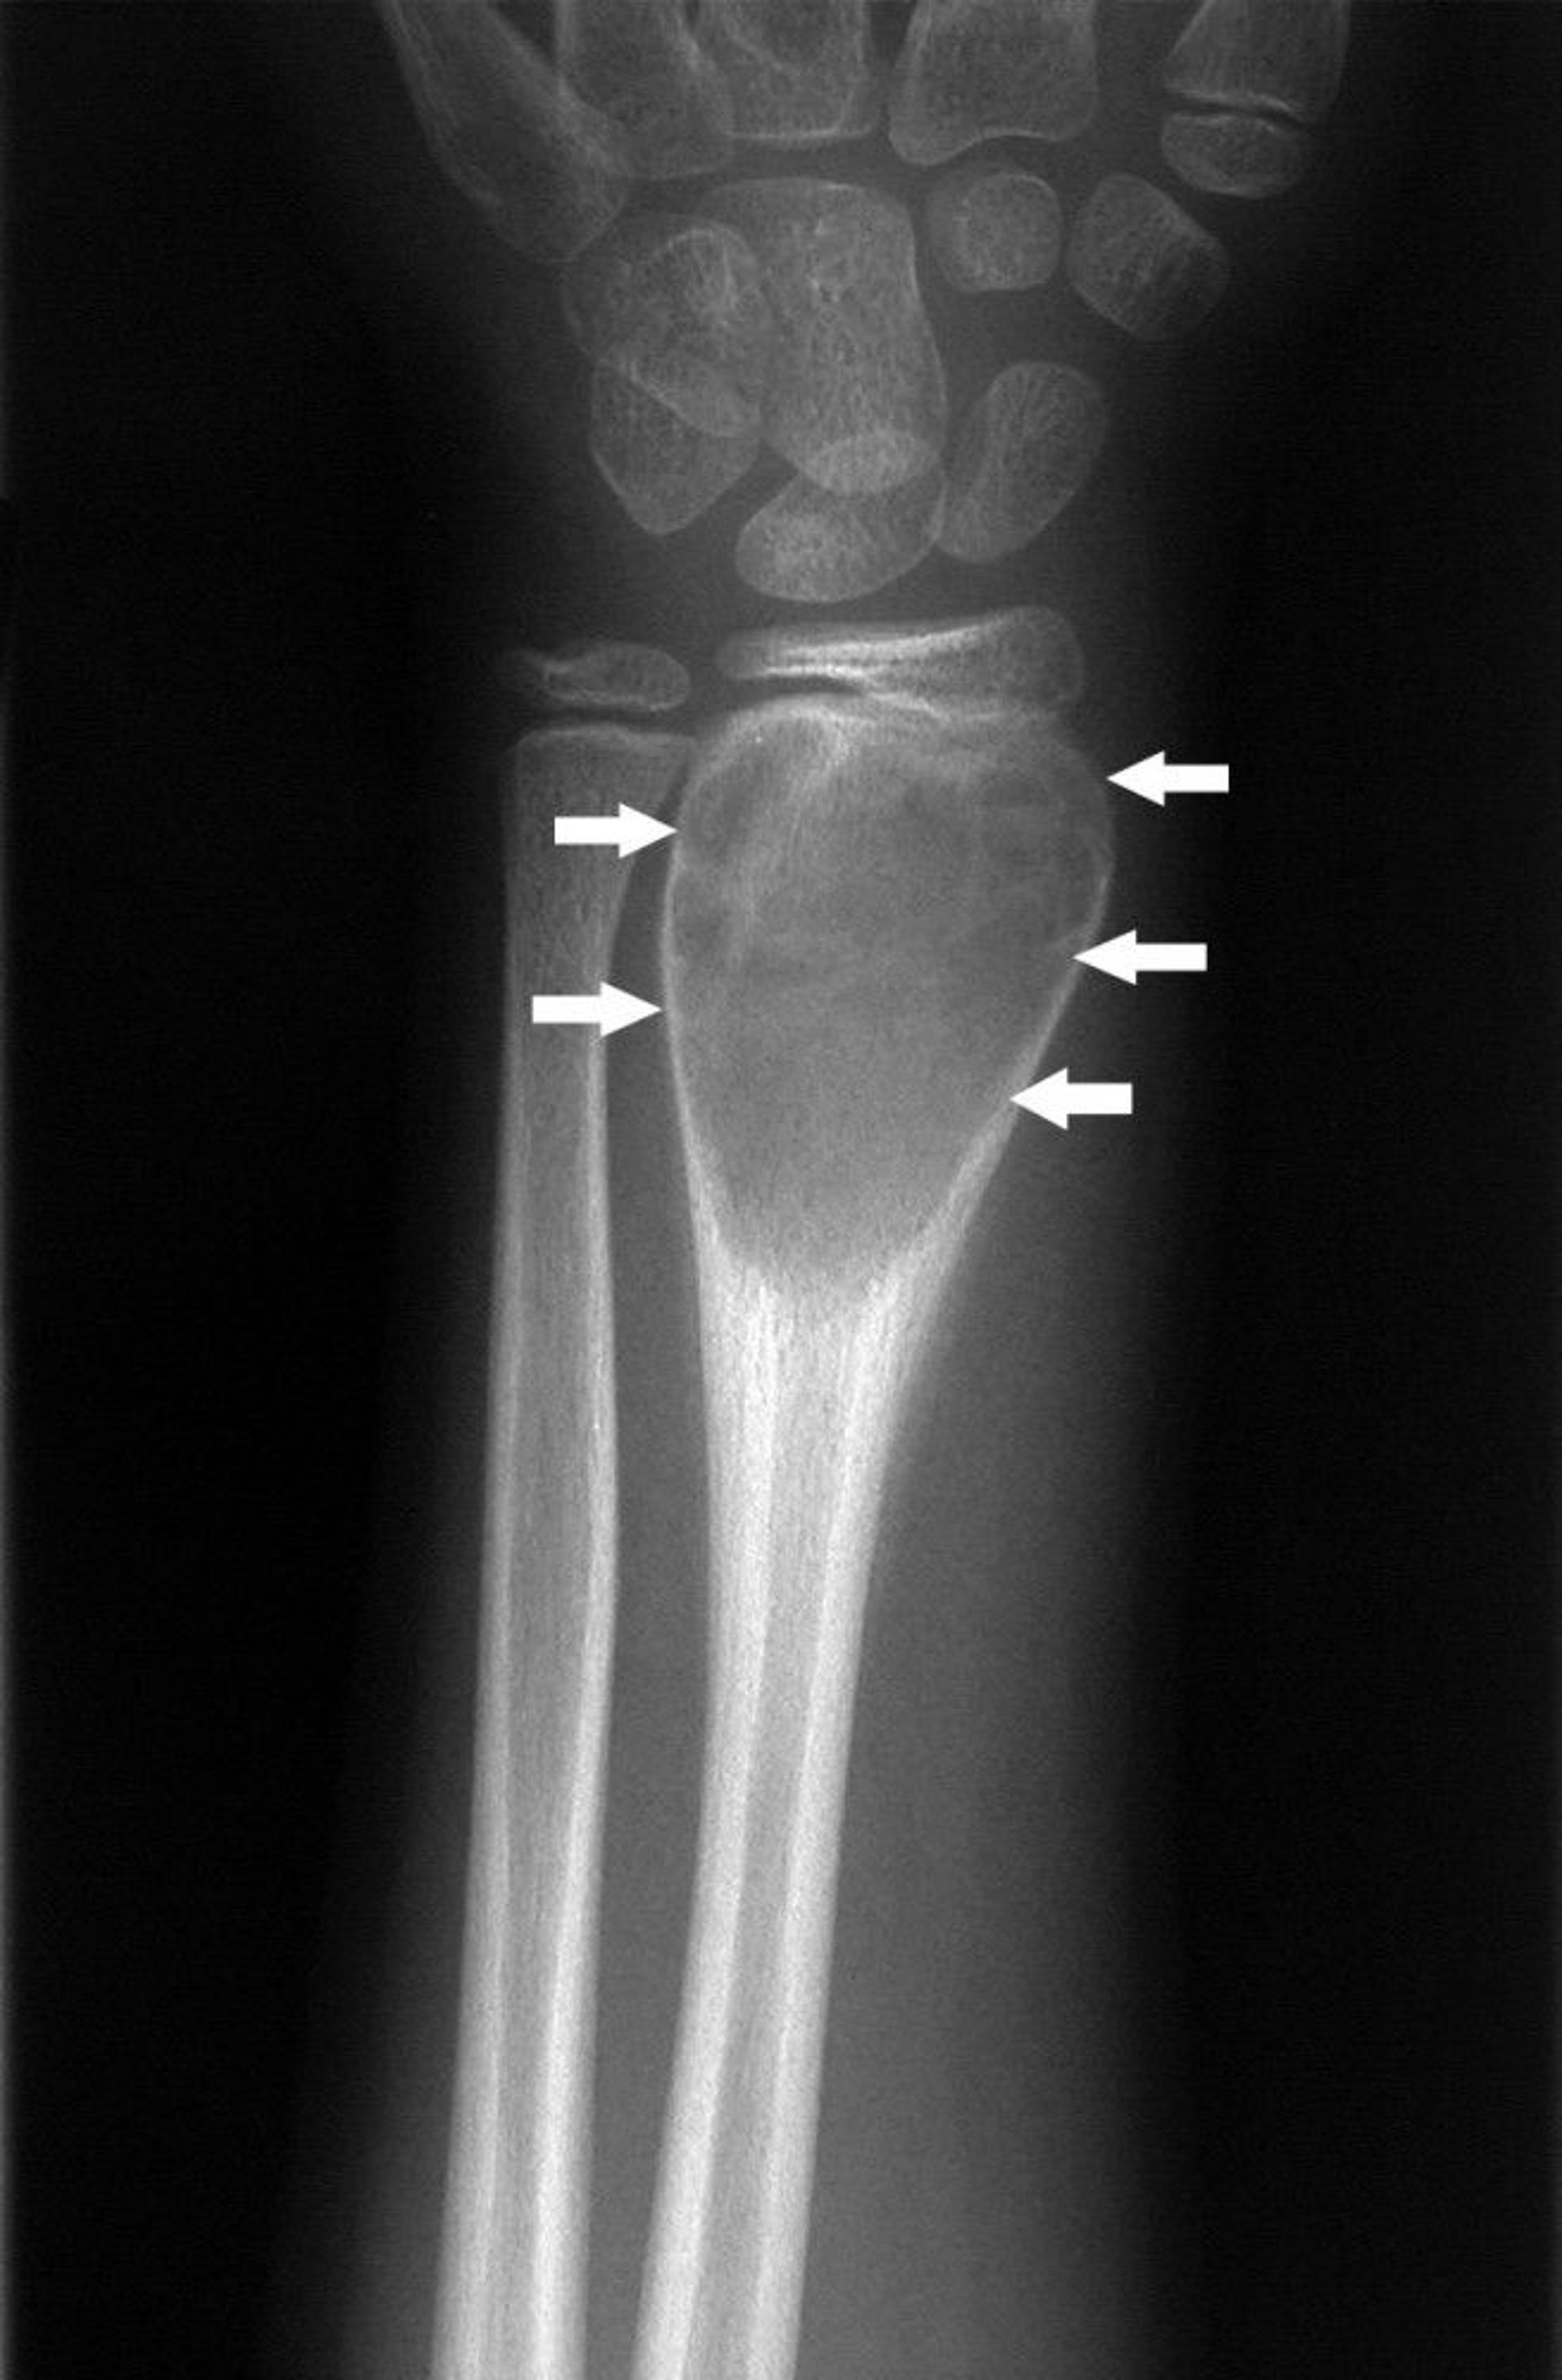

Sinar-x pergelangan tangan ini menunjukkan kista tulang yang menyebabkan ujung tulang membesar (panah).

Gambar milik Michael J. Joyce, MD, dan Hakan Ilaslan, MD.